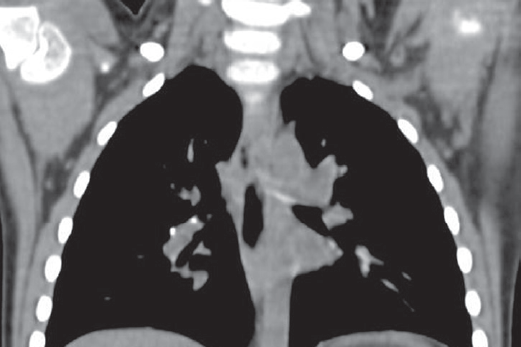

Проблема туберкулеза у детей раннего возраста в Российской Федерации остается актуальной в связи с анатомо-физиологическими особенностями этого периода детства, а также высокой распространенностью данного заболевания среди взрослых. Заболеваемость детей раннего возраста за 2015–2017 гг. в Санкт-Петербурге составила 7,1–5,3 на 100 тысяч населения. Для возрастной группы от 0 до 3 лет характерно то, что туберкулезный процесс часто переходит в стадию заболевания и не останавливается на латентном инфицировании. В наше исследование включены дети раннего возраста, которым диагноз туберкулеза был установлен в 2012–2017 гг. — всего 101 человек. Одна треть заболевших оказалась не вакцинирована БЦЖ, причем 41,9 % из них по причине перинатального контакта по ВИЧ и 22,5 % в связи с перинатальным контактом по ВИЧ + гепатит С. Каждый второй ребенок относился к группе социального риска. Контакт с больным туберкулезом — бактериовыделителем установлен у 64 % детей: лекарственная устойчивость по крайней мере к одному препарату встречалась у 70 %, в том числе у 19 % — множественная лекарственная устойчивость и у 11 % — широкая лекарственная устойчивость. Анализ иммунологической диагностики показал, что на момент выявления заболевания у детей проба Манту в 93 % случаев была положительной, но чаще умеренно выраженной, в то время как проба с аллергеном туберкулезным рекомбинантным (Диаскинтест) была положительной в 92 % случаев, преимущественно гиперергической или выраженной. При объективном обследовании у 79 % пациентов обнаружены симптомы интоксикации различной степени выраженности, у 50 % — микрополиадения, локальные симптомы — только у 13 %. В структуре диагнозов преобладал туберкулез внутригрудных лимфоузлов (67 %), генерализованные формы составили 9 %, внелегочные — 1 %. Осложненное течение наблюдалось в 38 % случаев. В результате лечения удалось добиться выздоровления у 98 детей, но было и 3 летальных исхода — все у невакцинированных грудных детей при наличии тяжелой сопутствующей патологии. Заключение: в настоящее время развитие активного туберкулеза у детей раннего возраста обусловлено увеличением количества не вакцинированных БЦЖ новорожденных — наиболее часто в связи с перинатальным контактом по ВИЧ, а также принадлежностью детей к социальной и эпидемиологической группе риска.